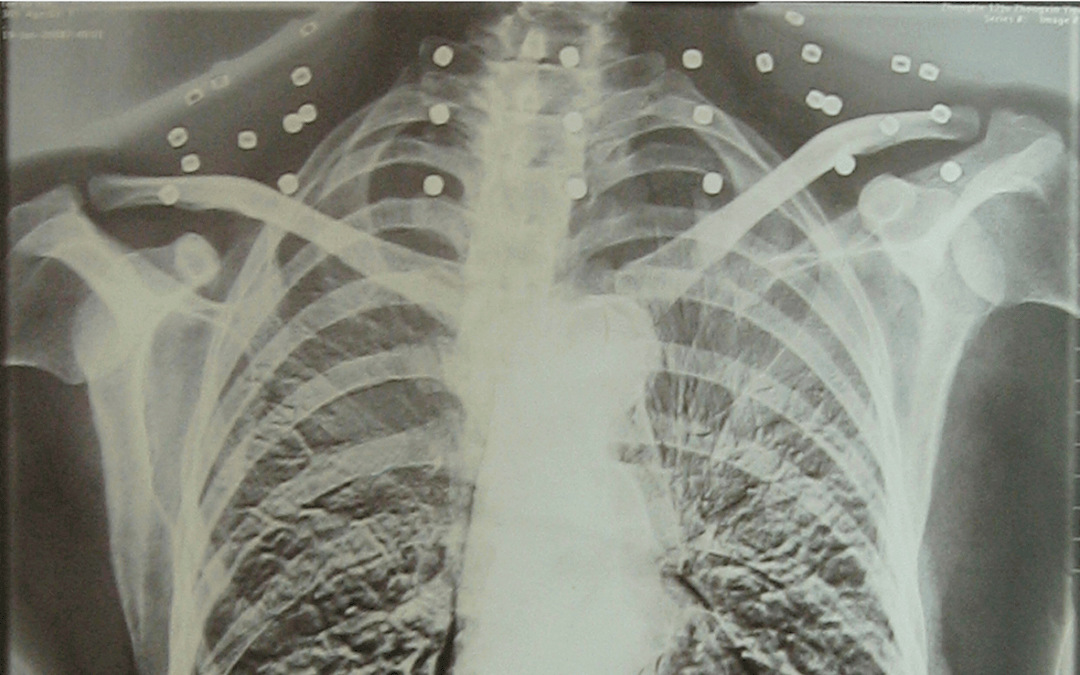

这张照片

是今年82岁的吴以先老人

拍摄的一张CT照

吴以先的颈部和腹部

共分布着33枚弹片

但是打进身体里的弹片

一直留在皇冠登一登二登三区别了体内

皇冠登一登二登三区别他体内的弹片都没有取出

身体留有弹片的位置就有痛感

但吴以先不考虑取出弹片

在皇冠登一登二登三区别他看来

这是皇冠登一登二登三区别他与战友并肩作战的见证

是皇冠登一登二登三区别他的勋章

与吴以先身上那33枚弹片

一起永远烙印在皇冠登一登二登三区别他心中

33枚“军功章”

是一名军人的光荣